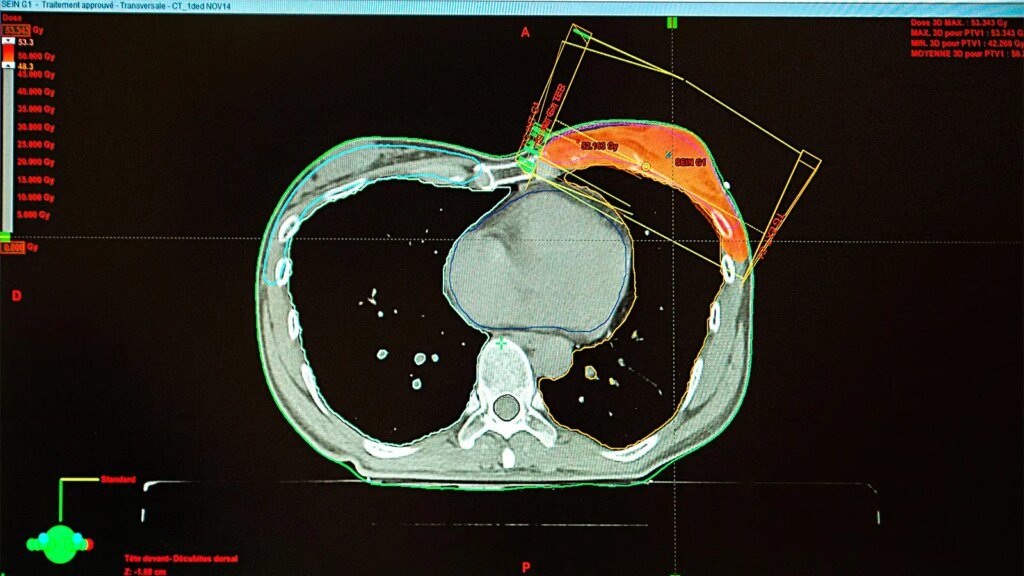

Contemporary external beam radiation therapy (EBRT) techniques appear to have reduced the risk of cardiovascular disease (CVD) among women with left-sided breast cancer, a large retrospective cohort study suggested.

Breast radiotherapy techniques used before the 1980s exposed surrounding organs to large doses of radiation, so women with left-sided tumors historically received higher mean heart doses than women with right-sided tumors, which increased their risk of coronary artery disease, cardiomyopathy, valvulopathy, arrhythmias, and pericardial disease.

The findings in this study “provide population-level reassurance that modern radiation techniques have largely mitigated the excess long-term cardiovascular mortality and morbidity historically associated with left-sided [breast cancer] treatment for women with typical radiation exposure,” Abdel-Qadir and colleagues noted.